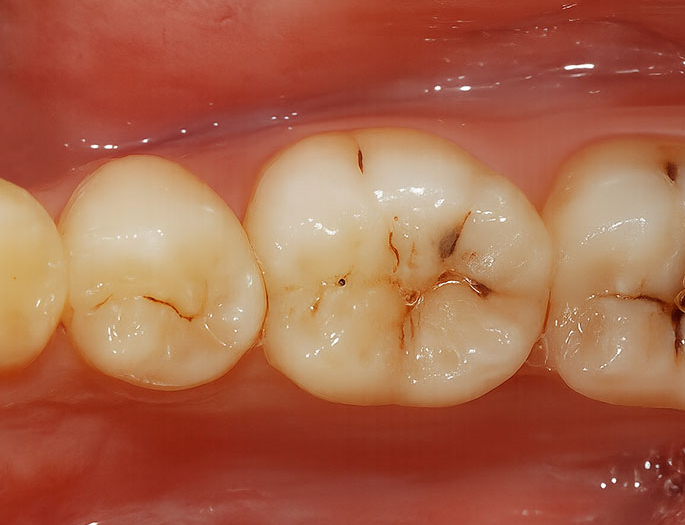

초기 단계라는 것은 표면이

살짝 까맣게 변색된 정도를 말하며

이런 경우 썩은 부분만 제거한 후

그 공간을 레진으로 채워 넣게 됩니다.

색은 주변 인접치와 맞출 수 있기 때문에

앞니에 사용해도 티가 나지 않습니다.

다만 교합력이 강한 어금니에는

적합하지 않을 수 있으며

우식의 범위가 넓거나 깊을 때는

이 방법만으로는 부족할 수 있으니

정기 검진을 통해 초기에 문제를 찾는 것이 좋습니다.